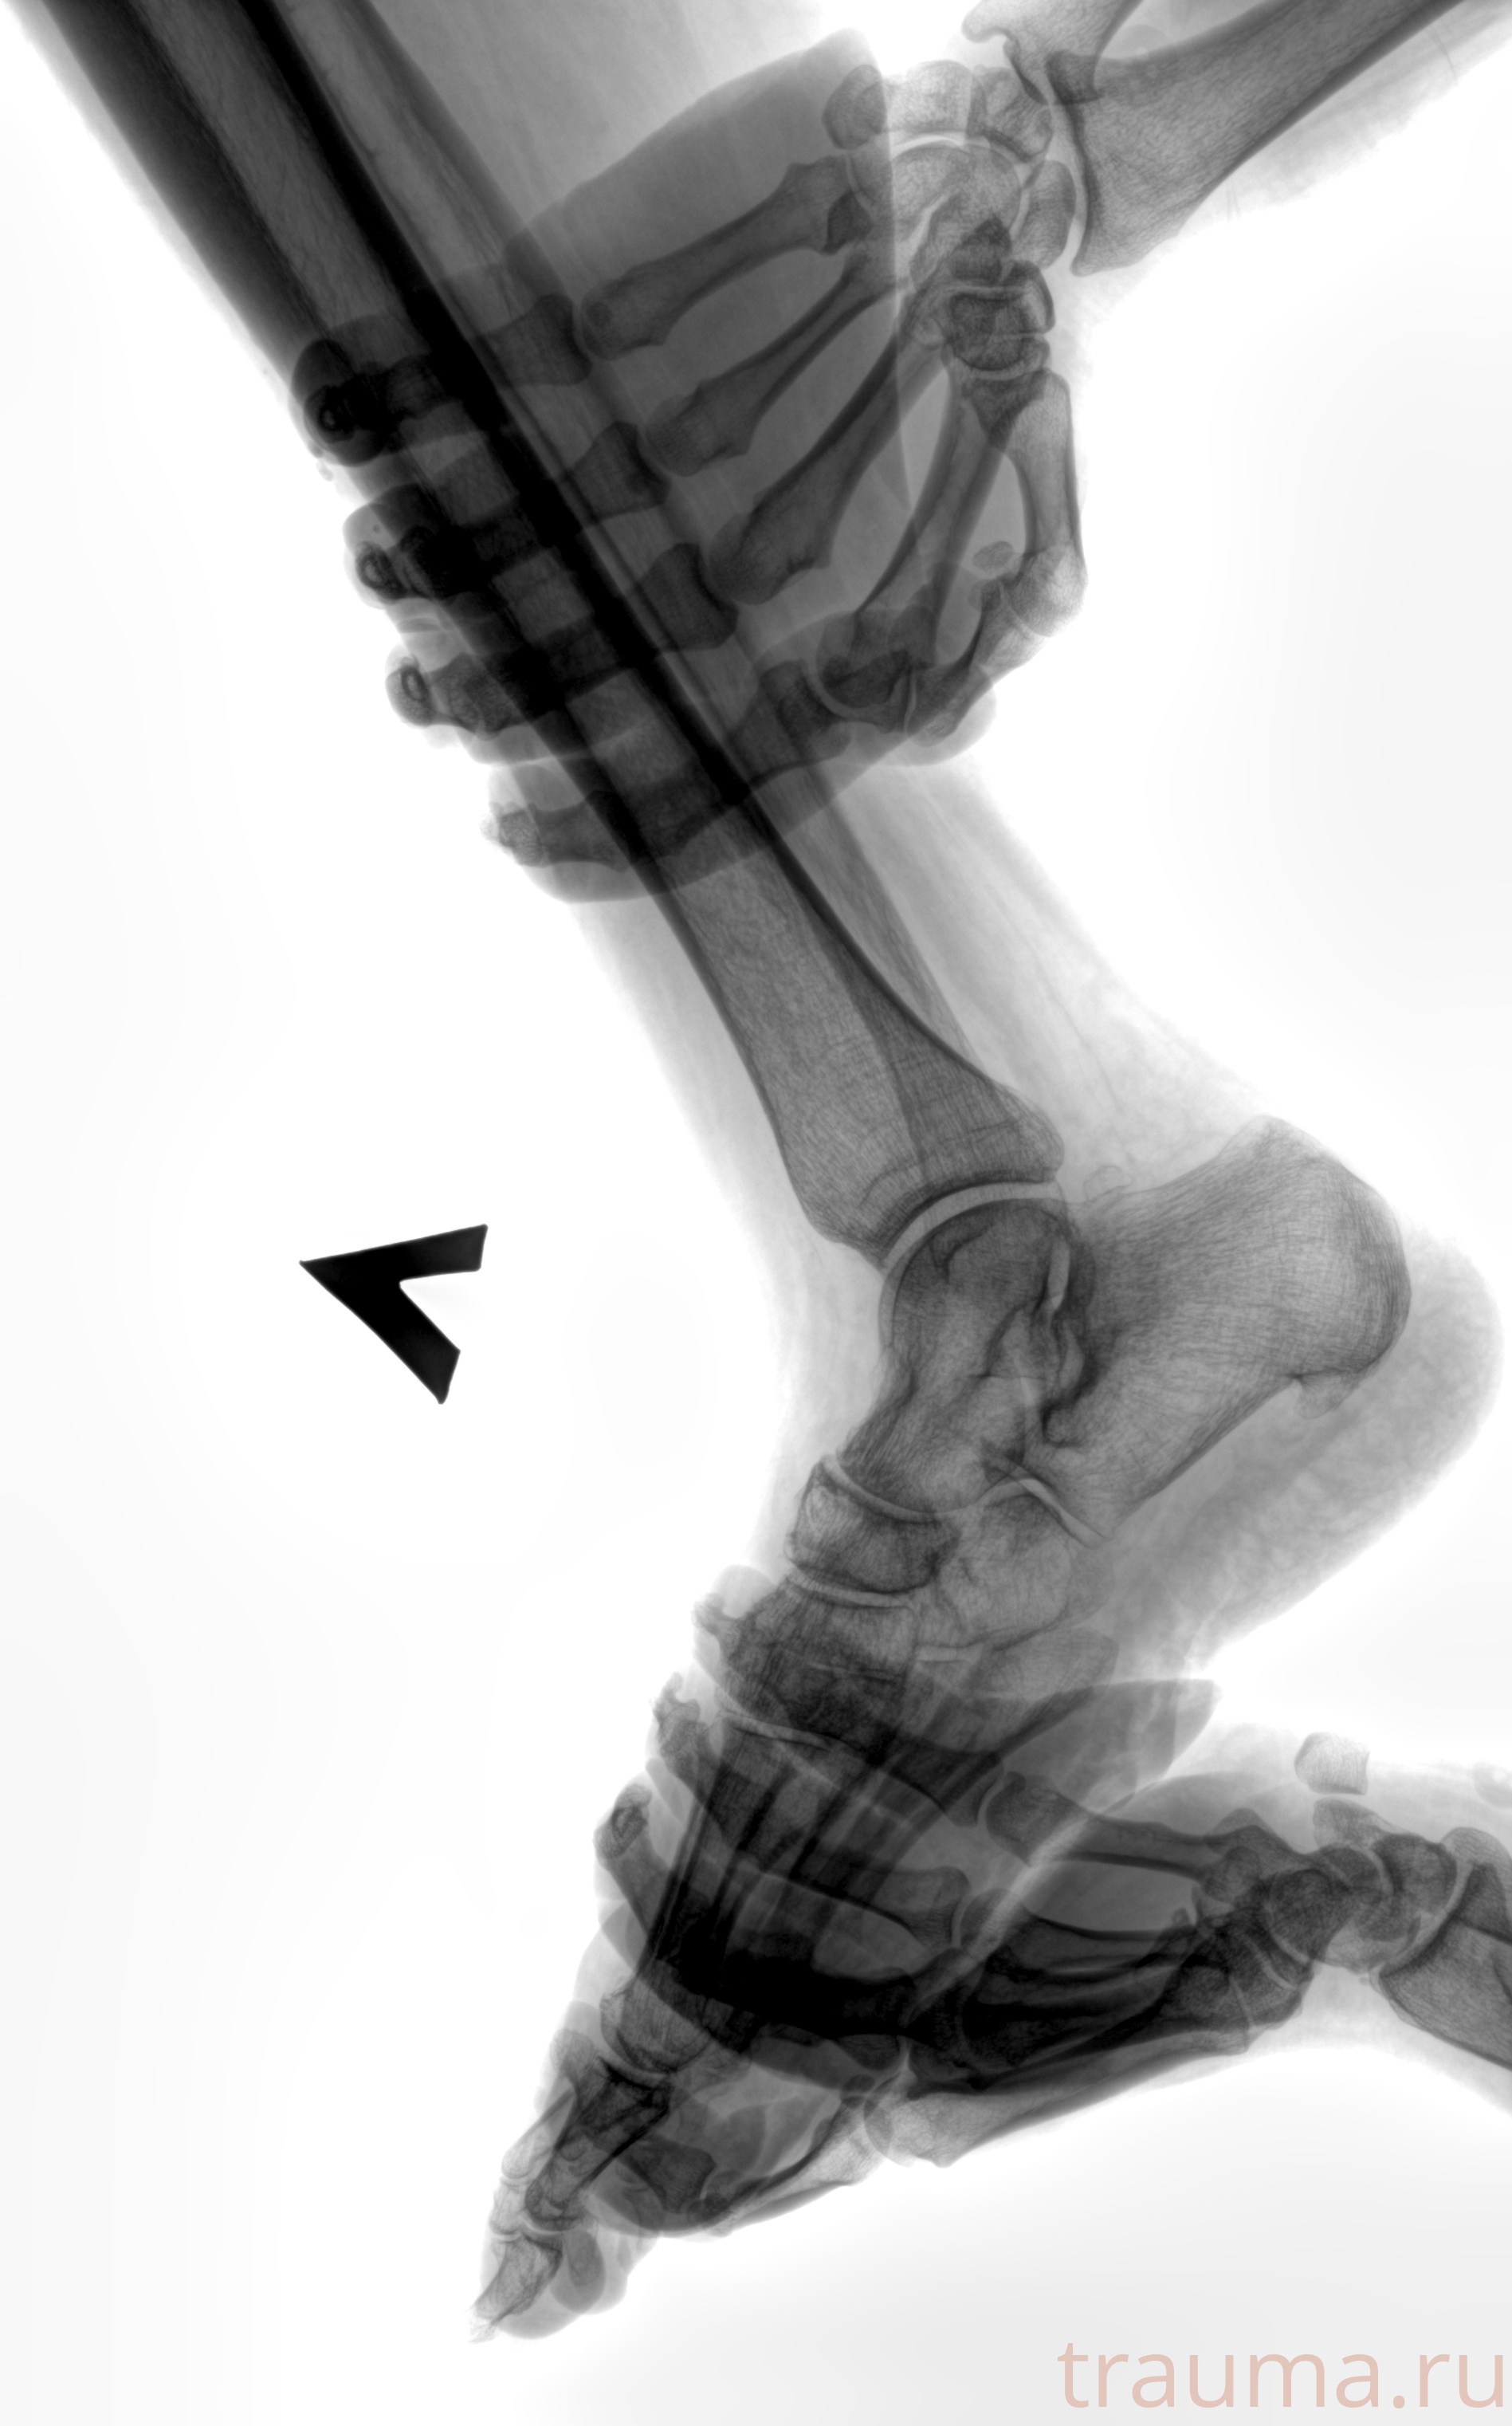

Рентген на дому: по вашему адресу приезжает врач-рентгенолог, травматолог-ортопед с мобильным рентгеновским аппаратом, проводит диагностику травмы или заболевания, делает необходимые рентгенограммы, дает рекомендации по дальнейшему лечению. Получить качественные снимки в домашних условиях возможно благодаря уникальной методике, разработанной МосРентген Центром для института  Склифосовского